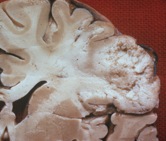

Early liquefactive necrosis

following an ischemic stroke

Brain tissue is very sensitive to insufficient oxygen and glucose supply, and is more susceptible to injury caused by ischemic bouts than most other tissue types. After three hours of ischemia permanent brain tissue damage occurs, and the affected area of the brain starts to undergo liquefactive necrosis.